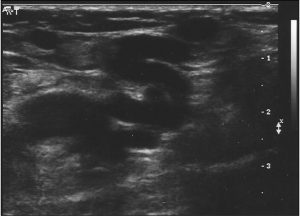

G — Атипичные варикозные вены, связанные с редкими перфорантами.

- Может встречаться в любой части нижней конечности.

- Например, рефлюкс в перфорантной вене колена можно выявить через расширение притоков коленного сустава.

- В некоторых случаях, перфорант коленного сустава, связанный с варикозом, может не иметь рефлюкса.